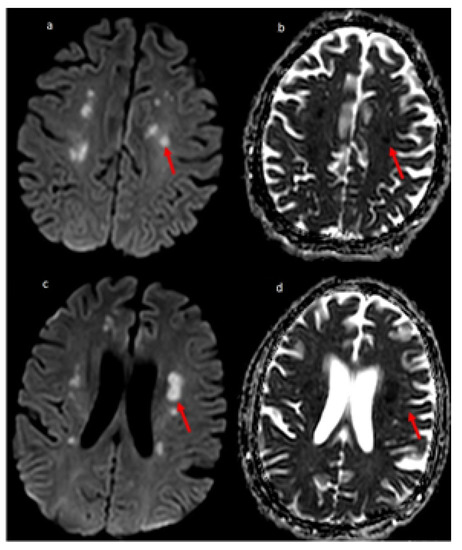

Overall, vascular pathology seen in imaging was significantly associated with fatality. A retrospective study by Benussi et al. also concluded that COVID-19 in patients with the cerebrovascular disease had significantly higher mortality than in-patients without COVID-19 [34]. The inflammatory pathology was significantly associated with the severity of the disease (refer Table 4 and Table 5). Severe COVID-19 patients may have developed neurological inflammation due to an intense inflammatory response or immunological phenomenon [13,35,36]. We present the MRI sections of two COVID-19 patients, one with multifocal ischemic stroke and another with encephalitis in Figure 2 and Figure 3, respectively.

Figure 2. 51-year-old man COVID-19 RT-PCR positive presented with dysarthria and change in mentation. MR Diffusion image (a) showing multiple foci of restricted diffusion (red arrow) involving centrum semiovale with the corresponding hypointense signal on ADC image (b), suggestive of embolic infarcts. (c) Showing multiple small foci of restricted diffusion (red arrow) involving centrum semiovale and periventricular white matter with the corresponding hypointense signal on ADC image (d), suggestive of embolic infarcts.